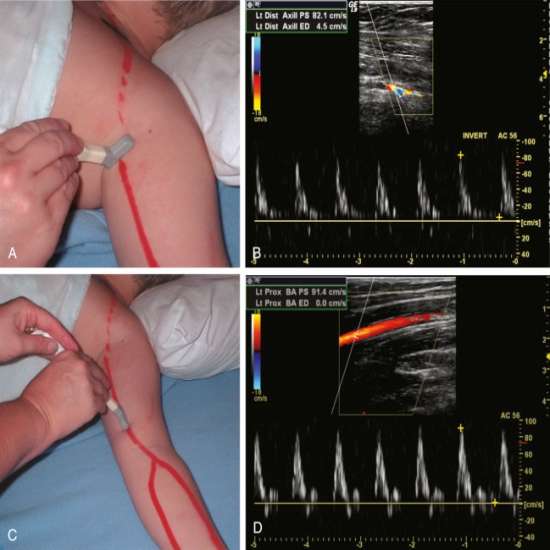

در این روش امواج فراصوت به بدن ارسال میشوند و پس از برخورد با گلبولهای خونی بازتاب مییابند؛ دستگاه با تحلیل این بازتابها، وضعیت جریان خون را به صورت رنگی (معمولاً قرمز و آبی بر اساس جهت و سرعت) نشان میدهد. این قابلیت، ارزیابی سریع هرگونه انسداد، لخته یا ناهنجاری عروقی را ممکن میسازد.

موارد استفاده و کاربردها